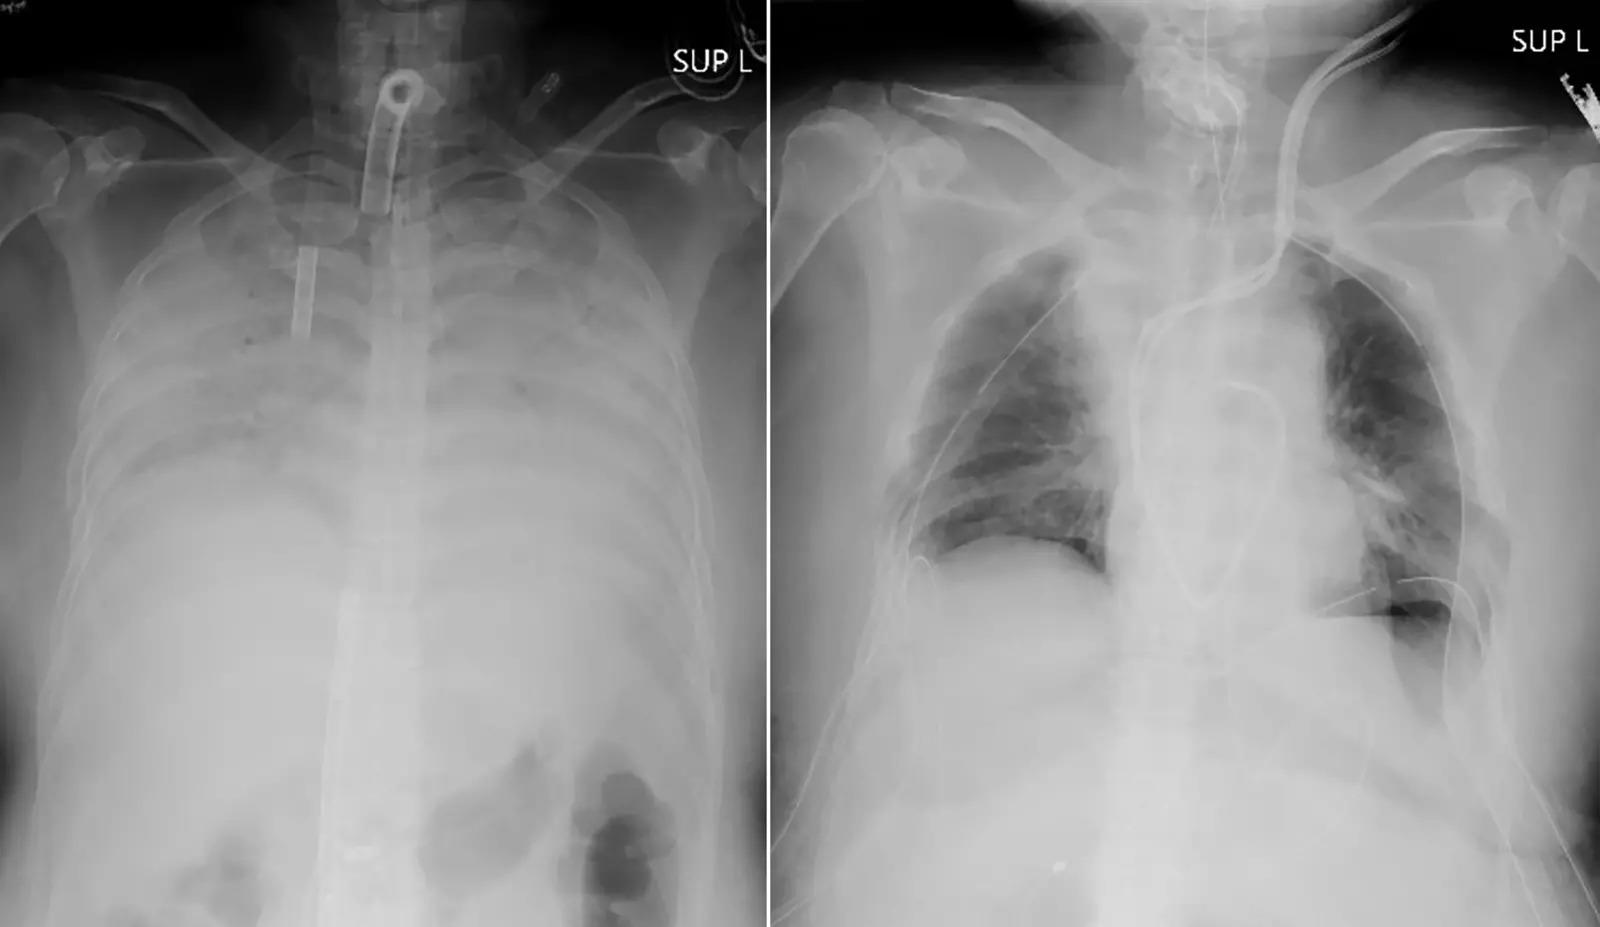

Again the more detrimental effect of L in public. We’ve all known for a long time that coronary heart disease affects the lungs. But this time it is said that in addition to the lungs, several other organs can be damaged in various ways in the body of the victims.

1. Heart ailments: People who have had heart disease before the onset of the disease or have problems with the metabolic system are more likely to spread the virus.

The virus causes the heart muscles of infected people to swell.

The study found that at least one-fourth of those hospitalized with coronary heart disease were more likely to have heart problems than those with severe symptoms. Some of the symptoms include low pulse rate, high heart rate, heartburn and rapid fatigue.

3. Kidney failure: In addition to other problems, various kidney problems have been observed in the affected people. The virus can infect several kidney cells.

As a result, kidney failure can stop.